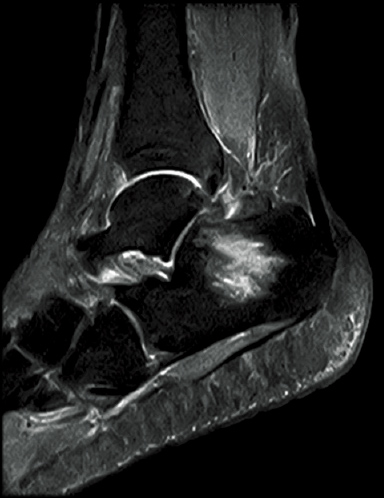

FatSep-T2*WI

FatSep-T2WI